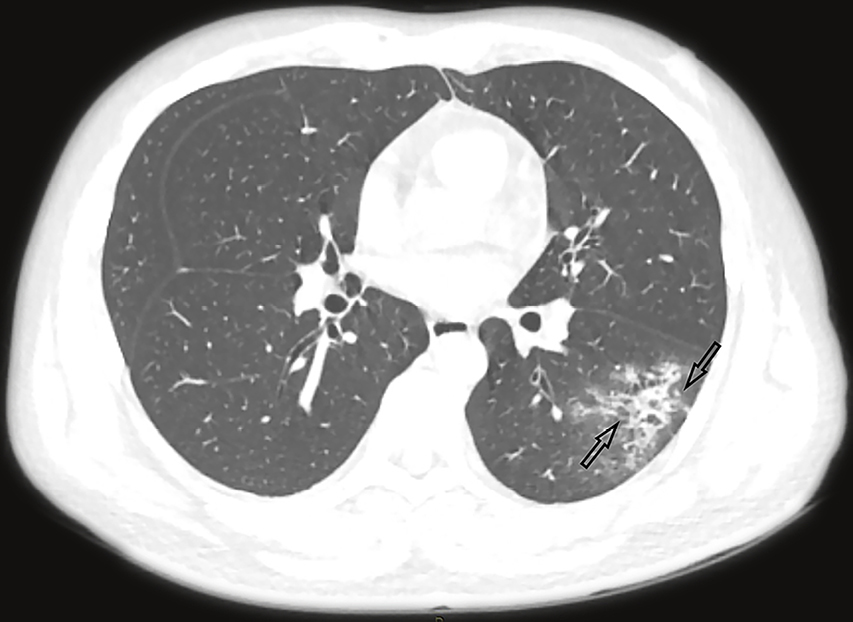

40+ Hrct Scan Chest Covid 19 PNG. Ct has a higher sensitivity but lower specificity and can play a role in the diagnosis and treatment of the disease. In an image sequence, the infection points may appear in some images and not be shown.

The diagnostic value of high resolution computerized tomography (hrct) scan chest in corona virus disease 2019. Most commonly was ggo that accounted for 120(88.9%). Ct has a higher sensitivity but lower specificity and can play a role in the diagnosis and treatment of the disease. Several full cases are reviewed, and the basic principle behind a scoring system is discussed.